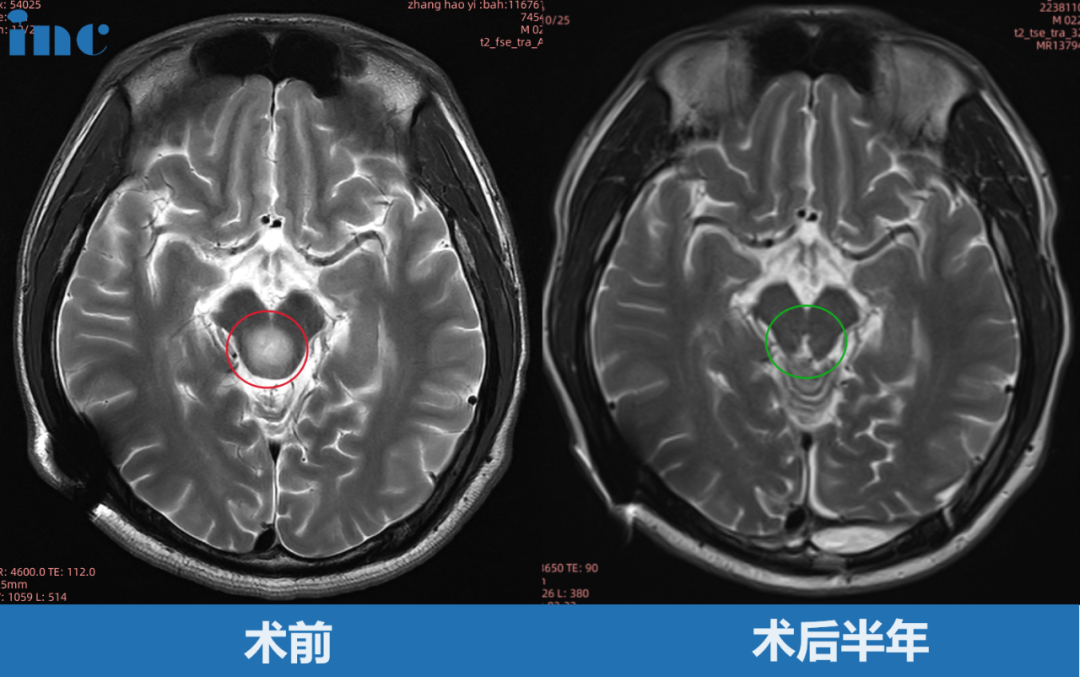

体检查出脑积水,症状加重再查已成胶质瘤

2016年,21岁的名校研究生张远(化名)在体检中偶然发现无症状脑积水,选择保守观察。2021年,头痛伴随眼球上视困难的神经症状。检查竟然发现:中脑顶盖区8mm占位性病变。2022 年 8 月张远病情再次加重,眼球活动受限,眼球向下运动困难,后脑勺偶然还会感到麻木或疼痛。复查磁共振提示肿瘤增大,此时肿瘤最大直径 12mm,一年半内生长4mm。然而,这个肿瘤不曾停止生长,2022 年 10 月复查核磁提示肿瘤增大,自行测量肿瘤大小约 18mm,两月内竟激增6mm!在一家人陷入恐慌焦虑之际,幸运的联系到了巴教授,成功手术。点击阅读:一台手术2个入路,一举歼灭脑干胶质瘤:研究生学霸术后2年半怎么样了?